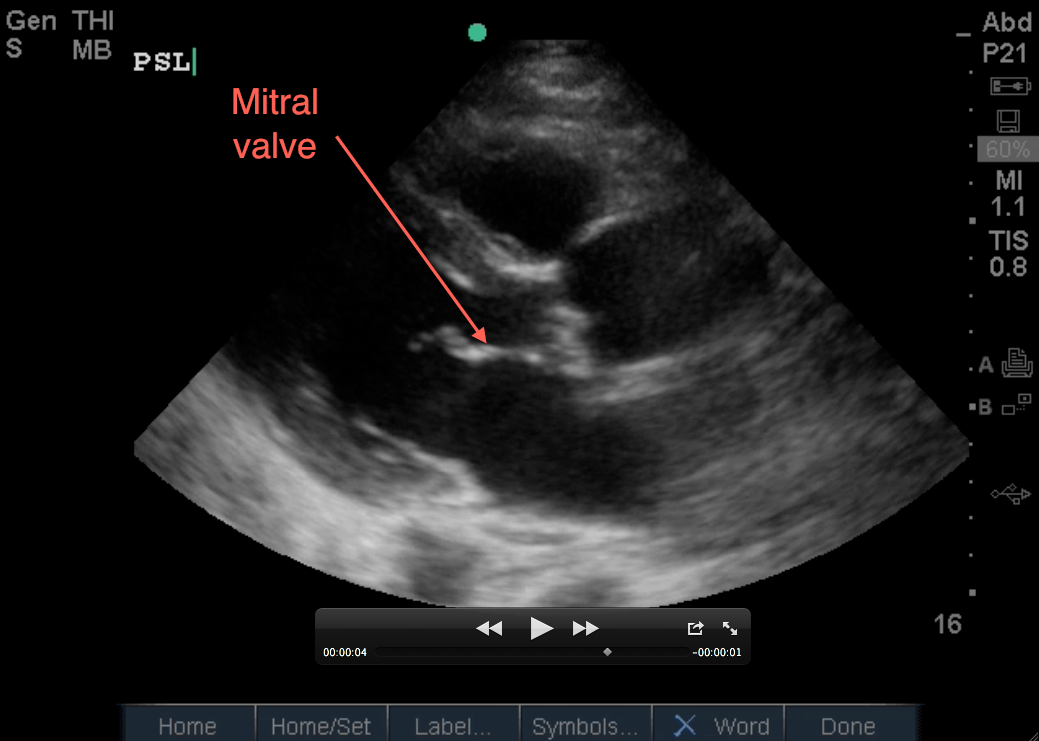

Despite the subxiphoid view being the traditional view for the FAST exam, the parasternal long view is becoming more of the ‘go-to’ window to evaluate for pericardial effusion. This may be due to several very relevant clinical factors: You simply cannot get a good subxiphoid view. An injury, foreign body, or abdominal pain does not allow for subxiphoid probe placement/pressure. Or you can differentiate pericardial fluid from pleural fluid in the parasternal long view.

Tips for Parasternal Long View:

As far as patient positioning, if you’ve already evaluated the RUQ and LUQ (so as to not affect free fluid evaluation) and the patient is able to turn into a left lateral decubitus position, it will help bring the heart closer to the chest wall for visualization. This can be difficult, or impossible, in trauma patients, so the below tips may help:

1. Start high and start medial – Place your phased array probe just next to the sternum, starting just under the clavicle. If you don’t see the heart there, slide down a rib space, and fan through that space to find the heart. Continue sliding down rib spaces, until you find it.

2. Slowly change the angle of your probe (up and down) when you’re assessing each rib space as described above. ‘Slowly’ is the key word here. If you’re angling downward too much in a rib space and see the PSL heart, you may need to just slide down a rib space. If that makes the image worse, slide back up.

3. Slowly rotate your probe while keeping the angle described above (clockwise/counterclockwise depending on whether you use the right shoulder or the left hip to direct your probe marker). Rotate until you visualize the longitudinal view of the left side of the heart.

4. Slide your probe medially/laterally only if you need to in order to center the aortic and mitral valves on your screen.

5. Ensure adequate depth in order to distinguish a left sided pleural effusion from a pericardial effusion. This will allow visualization of the descending thoracic aorta seen in its transverse view just deep to the heart, which is your landmark in differentiating pleural effusion from pericardial effusion. Pleural effusion will travel posterior to the aorta while pericardial effusion will travel anterior to it (and possibly circumferentially around the heart).